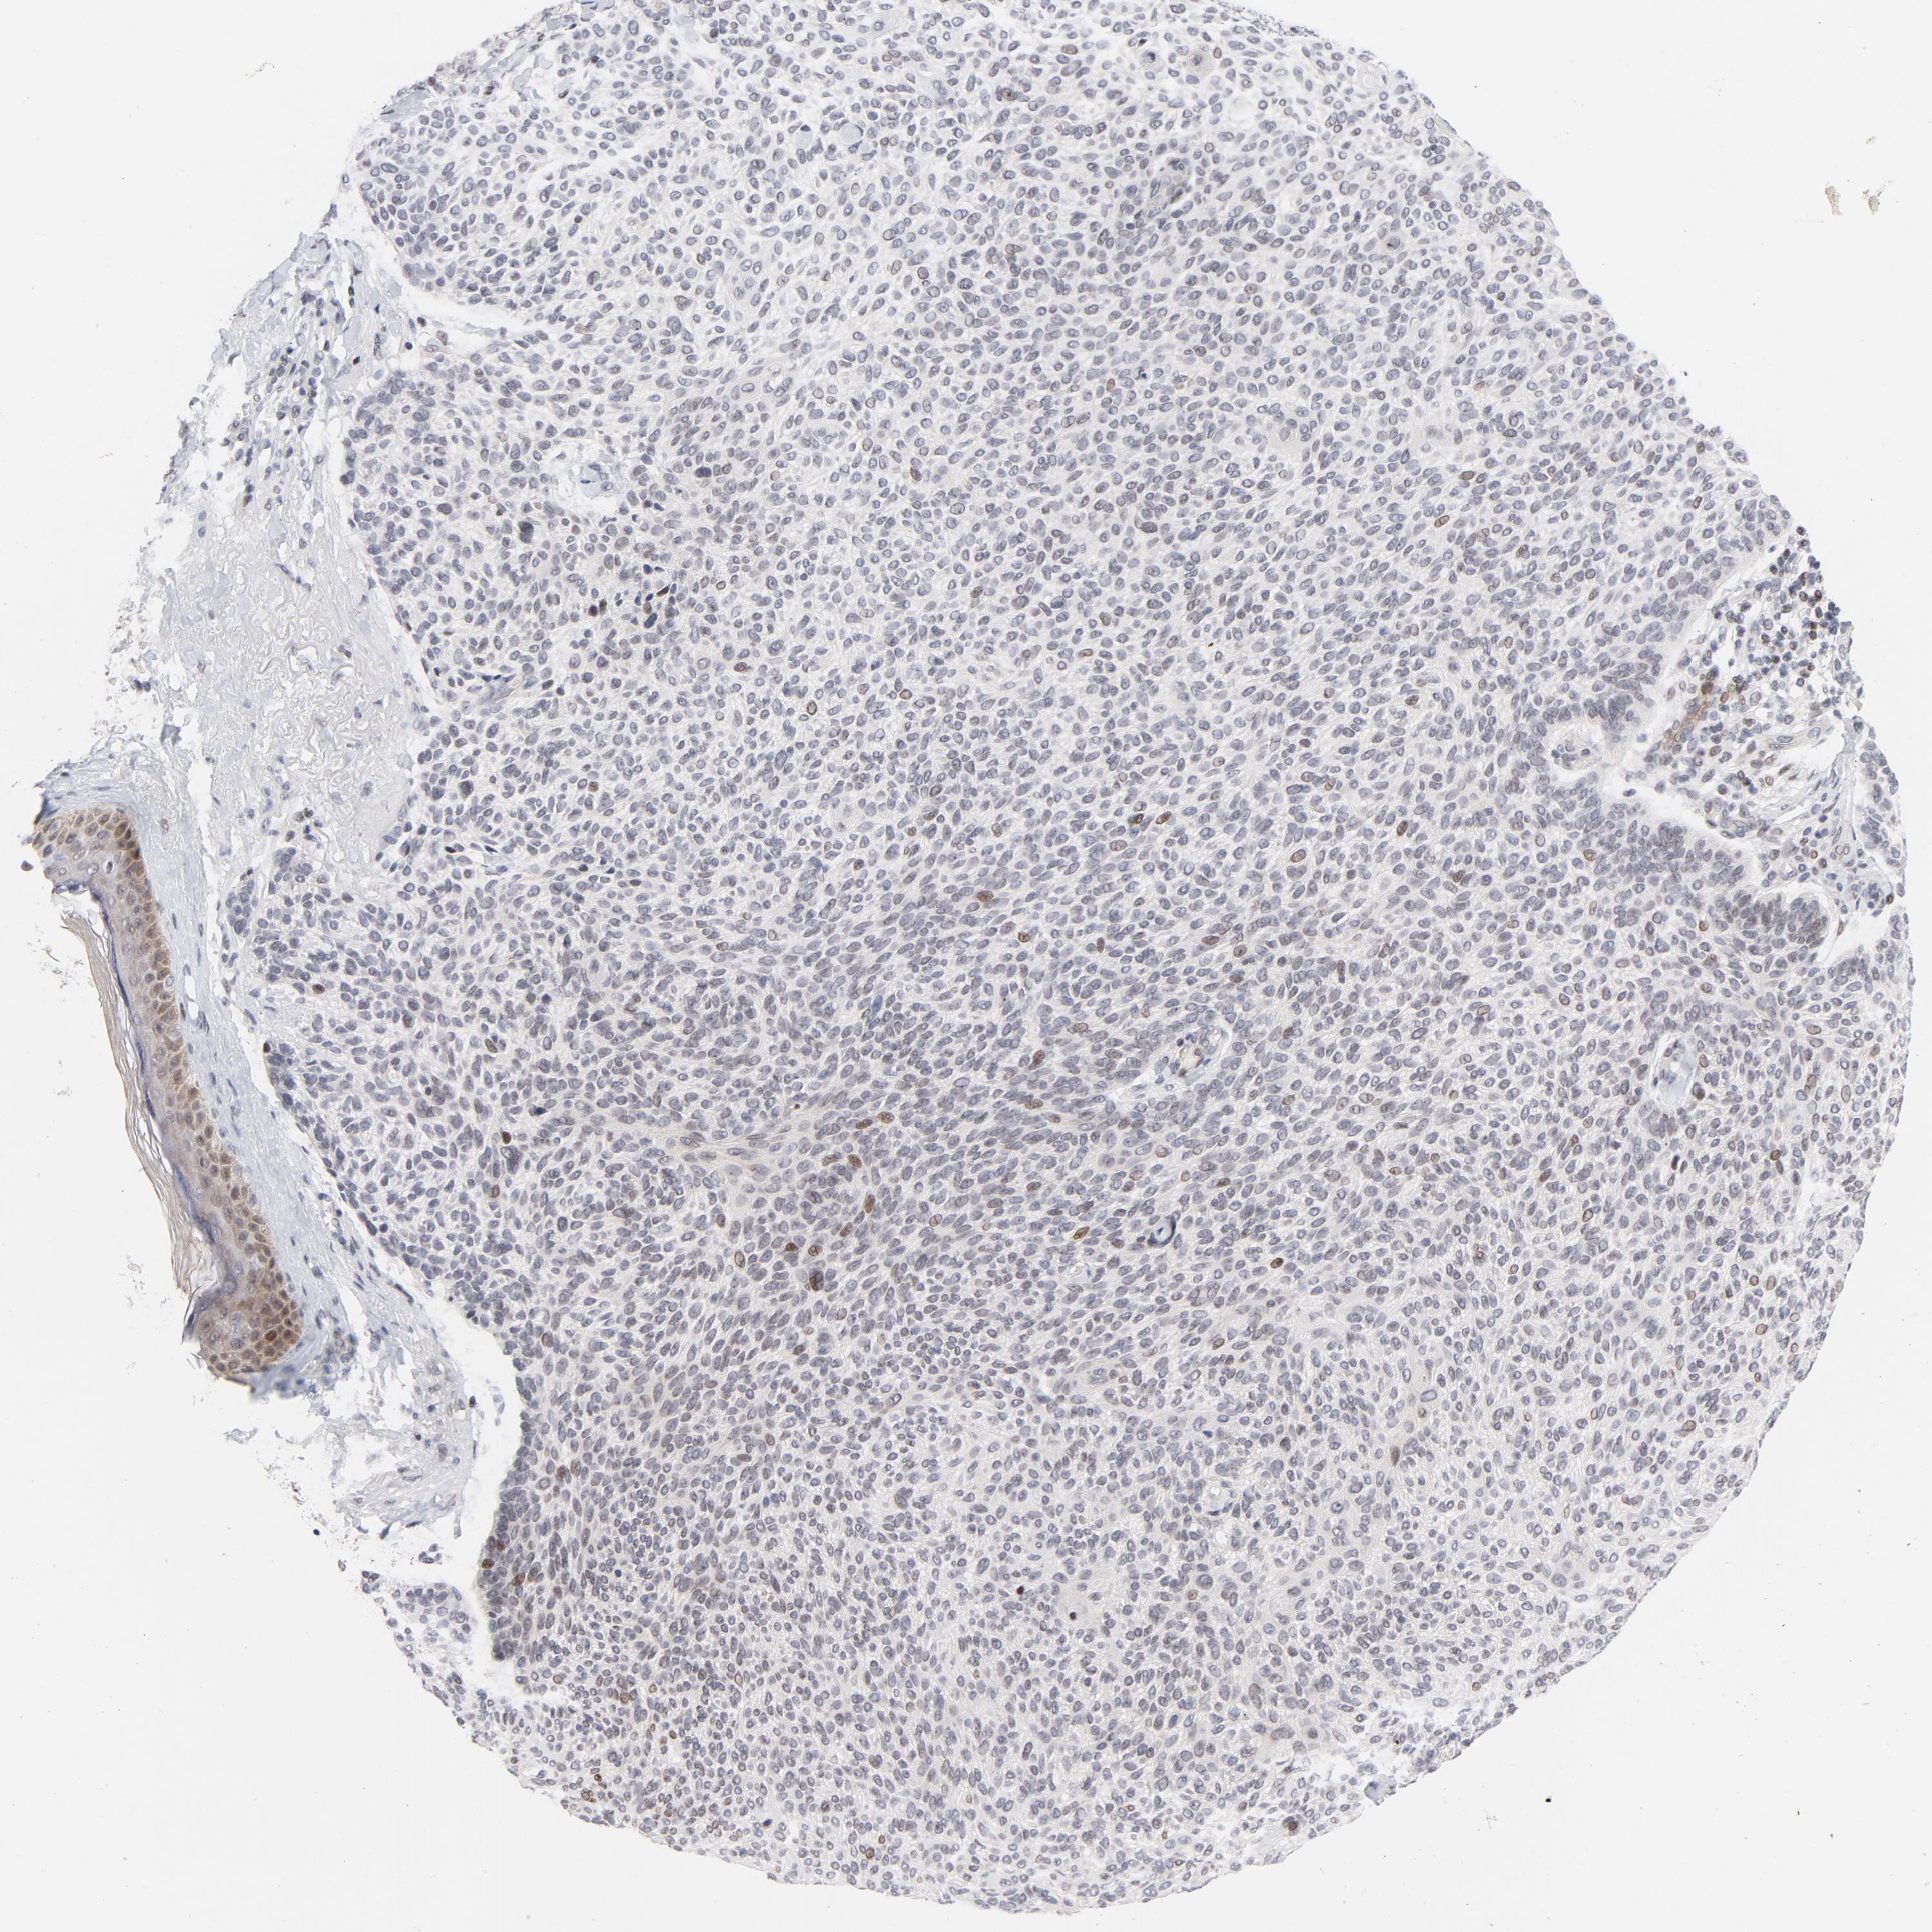

SKIN CANCER - Protein expressioni

A mouse-over function shows sample information and annotation data. Click on an image to view it in a full screen mode. Samples can be filtered based on level of antibody staining by selecting one or several of the following categories: high, medium, low and not detected. The assay and annotation is described here.

Antibody stainingi

Antibody staining in the annotated cell types in the current human tissue is reported as not detected, low, medium, or high, based on conventional immunohistochemistry profiling in selected tissues. This score is based on the combination of the staining intensity and fraction of stained cells.

Each image is clickable and will lead to virtual microscopy that enables deeper exploration of all samples and also displays staining intensity scores, fraction scores and subcellular localization as well as patient and tissue information for each sample.

Antibody HPA052625

Staining

Not detected

Negative

None

Nuclear

Basal cell carcinoma

BCC, low aggressive